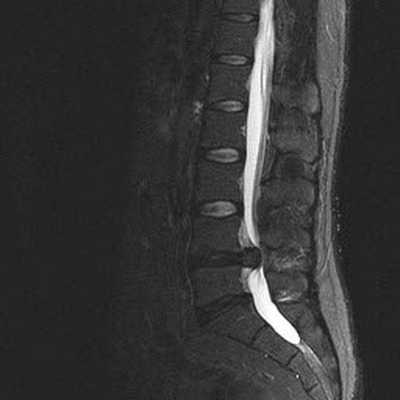

Ведущими в МРТ позвоночника всегда являются сагиттальная (вдоль тела) а аксиальная (поперечная) плоскости, дополнительной может быть корональная (фронтальная) плоскость. Физические основы МРТ и получение МРТ изображения изложены в наших статьях, однако, они предназначены для подготовленного читателя. Разглядывая МРТ изображение позвоночника, Вы увидите, что спинномозговая жидкость (ликвор) на одних из них светлый (почти белый), на других, наоборот, темный. Так можно различить Т2-взвешенные и Т1-взвешенные МРТ изображения. Очень важно понимать, что это не негатив и позитив, а МРТ изображения, зависимые от разных физических характеристик, и потому несущие в себе разную информацию. На снимке (вернее сказать, отпечатке) или на CD диске, сняты или записаны серии однотипных по способу получения МРТ изображений позвоночника. Срезы идут друг за другом, например, справа налево в сагиттальной плоскости. Обычно для облегчения понимания где проходит данный срез в углу картинки дается референтное изображение, оно показывает линию этого МРТ среза в другой, перпендикулярной ему плоскости. Иногда делается дополнительное референтное МРТ изображение на котором показаны все срезы с их нумерацией. Зазор между срезами меньше 1 мм или вовсе отсутствует. Толщина среза выбирается оптимальной в зависимости от исследуемого отдела позвоночника, плоскости и МРТ аппарата. Обычно при МРТ позвоночника она 3-4 мм. В любом случае, выбираемый оператором или врачом протокол МРТ (то есть набор плоскостей и последовательностей), соответствует задачам данного МРТ исследования. Оценка качества МРТ изображения не может быть осуществлена ни пациентом, ни врачом-клиницистом. Заключение, данное врачом-рентгенологом, подразумевает, что само изображение было приемлимым для выводов. Хотелось бы особо подчеркнуть, что Заключение в конце Описания, выдаваемое пациенту, не является диагнозом, а лишь выводами врача- рентгенолога на основе интерпретации им изображений. Диагноз ставится врачом-клиницистом на основании всех имеющихся медицинских данных - жалоб, клинического осмотра, заключений других специалистов, лабораторных анализов, заключений по МРТ и другим изображениям. При этом расхождения между заключениями по результатам разных исследований явление вполне нормальное.

МРТ позвоночника. Сагиттальная Т2-взвешенная МРТ, срединный срез поясничного отдела. Показана нумерация позвонков, измерения позвоночного канала (черная линия). Т- дуральный мешок с ярким ликвором. L- желтая связка. Sacrum - крестец. D - межпозвоночный диск. Голубым выделен остистый отросток, желтым - тело позвонка, Голубые точки - ход корешков.